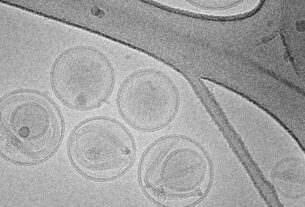

En voluntarios sanos, se evaluó la bioseguridad mediante TMRE y anexina V en leucocitos.

In vivo, ambos métodos aumentaron la actividad mitocondrial y la apoptosis en leucocitos de pacientes con ERC.